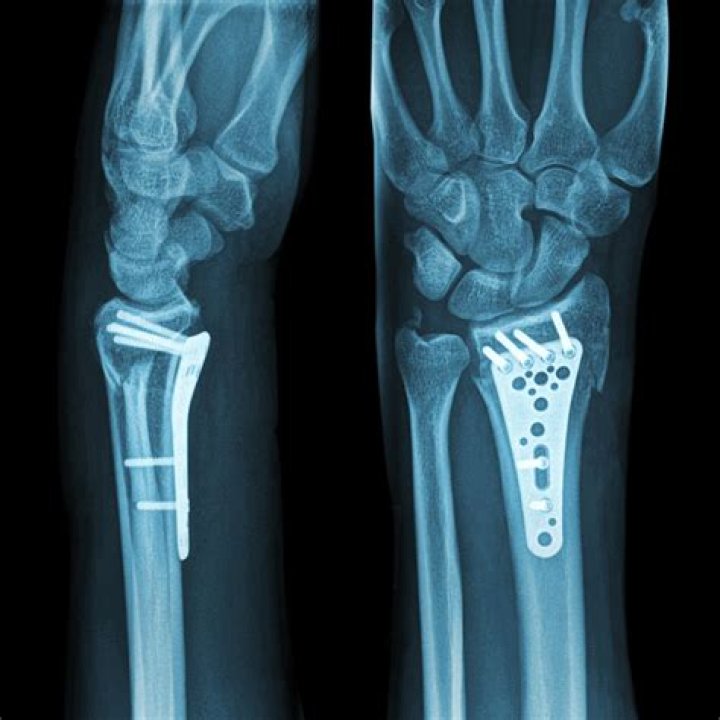

When a distal radius fracture is complex or unstable, it will most likely require a surgical approach to ensure the fracture stays in place during the healing process.

How do you fix a distal radius fracture?

Nonsurgical Treatment If the distal radius fracture is in a good position, a splint or cast is applied. It often serves as a final treatment until the bone heals. Usually a cast will remain on for up to six weeks. Then you will be given a removable wrist splint to wear for comfort and support.